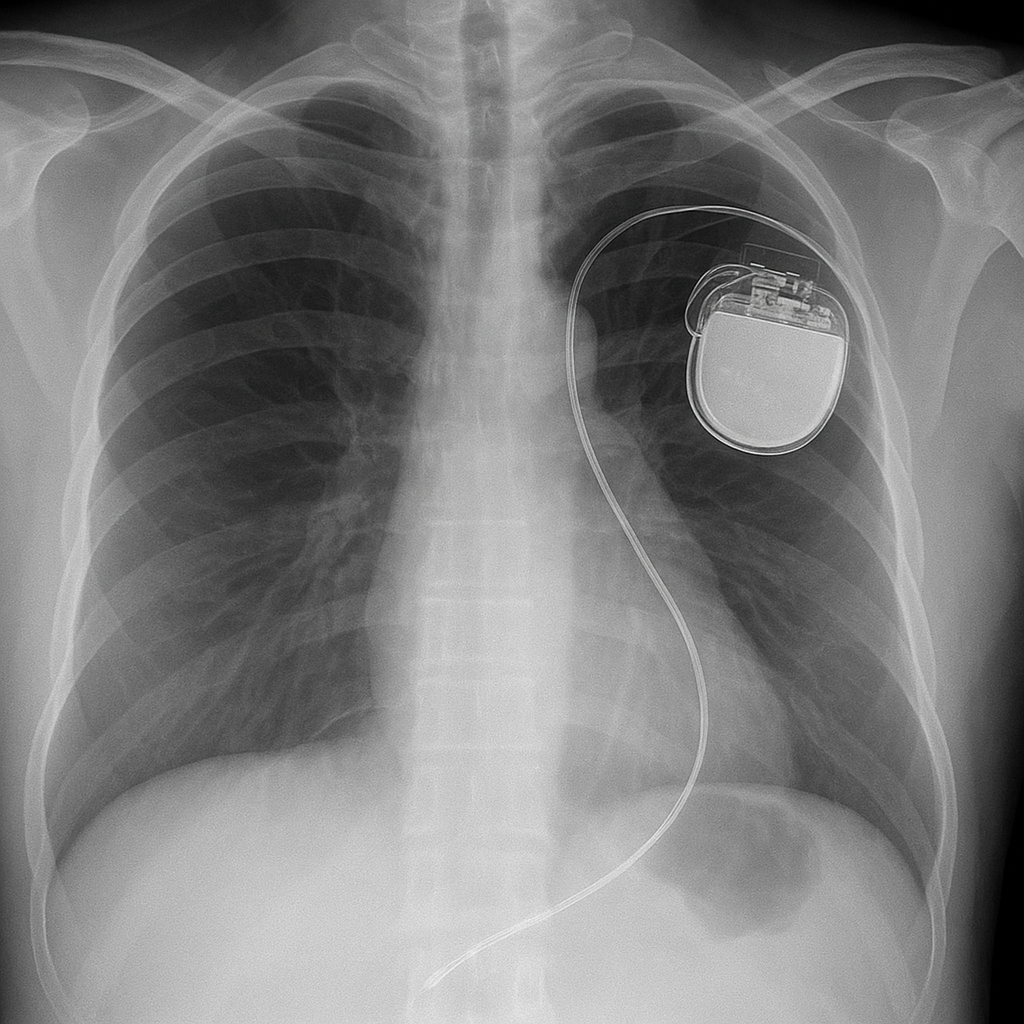

Pacemaker Implantation

A pacemaker is a compact, implantable device designed to regulate the heart’s electrical signals. It is typically recommended for individuals with slow, irregular, or temporarily halted heartbeats. By delivering controlled electrical impulses, the pacemaker helps maintain a consistent heart rhythm, boosts energy, reduces fatigue, and supports a better overall quality of life.